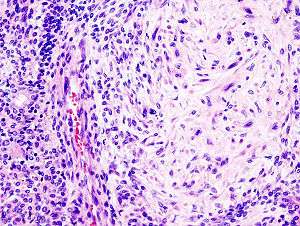

| Pleomorphic adenoma consists of mixed epithelial (left) and mesenchymal cell components (right). The latter often exhibits myxofibrous appearance and in some instances shows chondromatous differentiation. | |

Histologically, it is highly variable in appearance, even within individual tumors. Classically it is biphasic and is characterized by an admixture of polygonal epithelial and spindle-shaped myoepithelial elements in a variable background stroma that may be mucoid, myxoid, cartilaginous or hyaline. Epithelial elements may be arranged in duct-like structures, sheets, clumps and/or interlacing strands and consist of polygonal, spindle or stellate-shaped cells (hence pleiomorphism). Areas of squamous metaplasia and epithelial pearls may be present. The tumor is not enveloped, but it is surrounded by a fibrous pseudocapsule of varying thickness. The tumor extends through normal glandular parenchyma in the form of finger-like pseudopodia, but this is not a sign of malignant transformation.